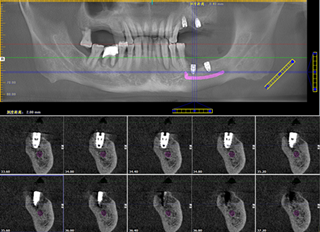

一期种牙之后的牙齿